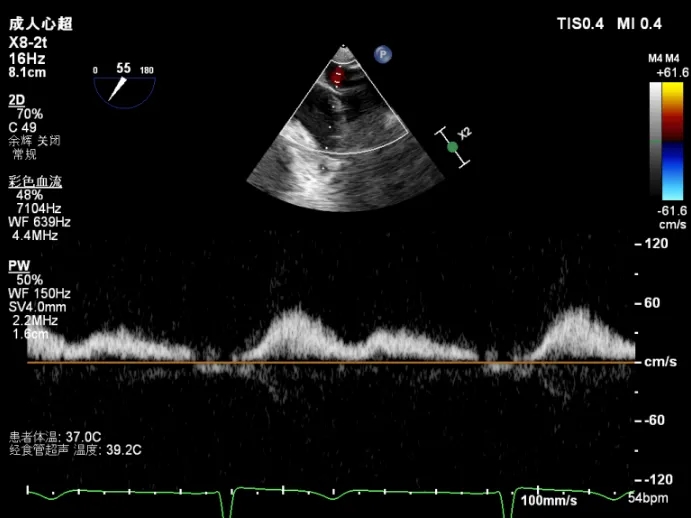

肺静脉逆流明显改善